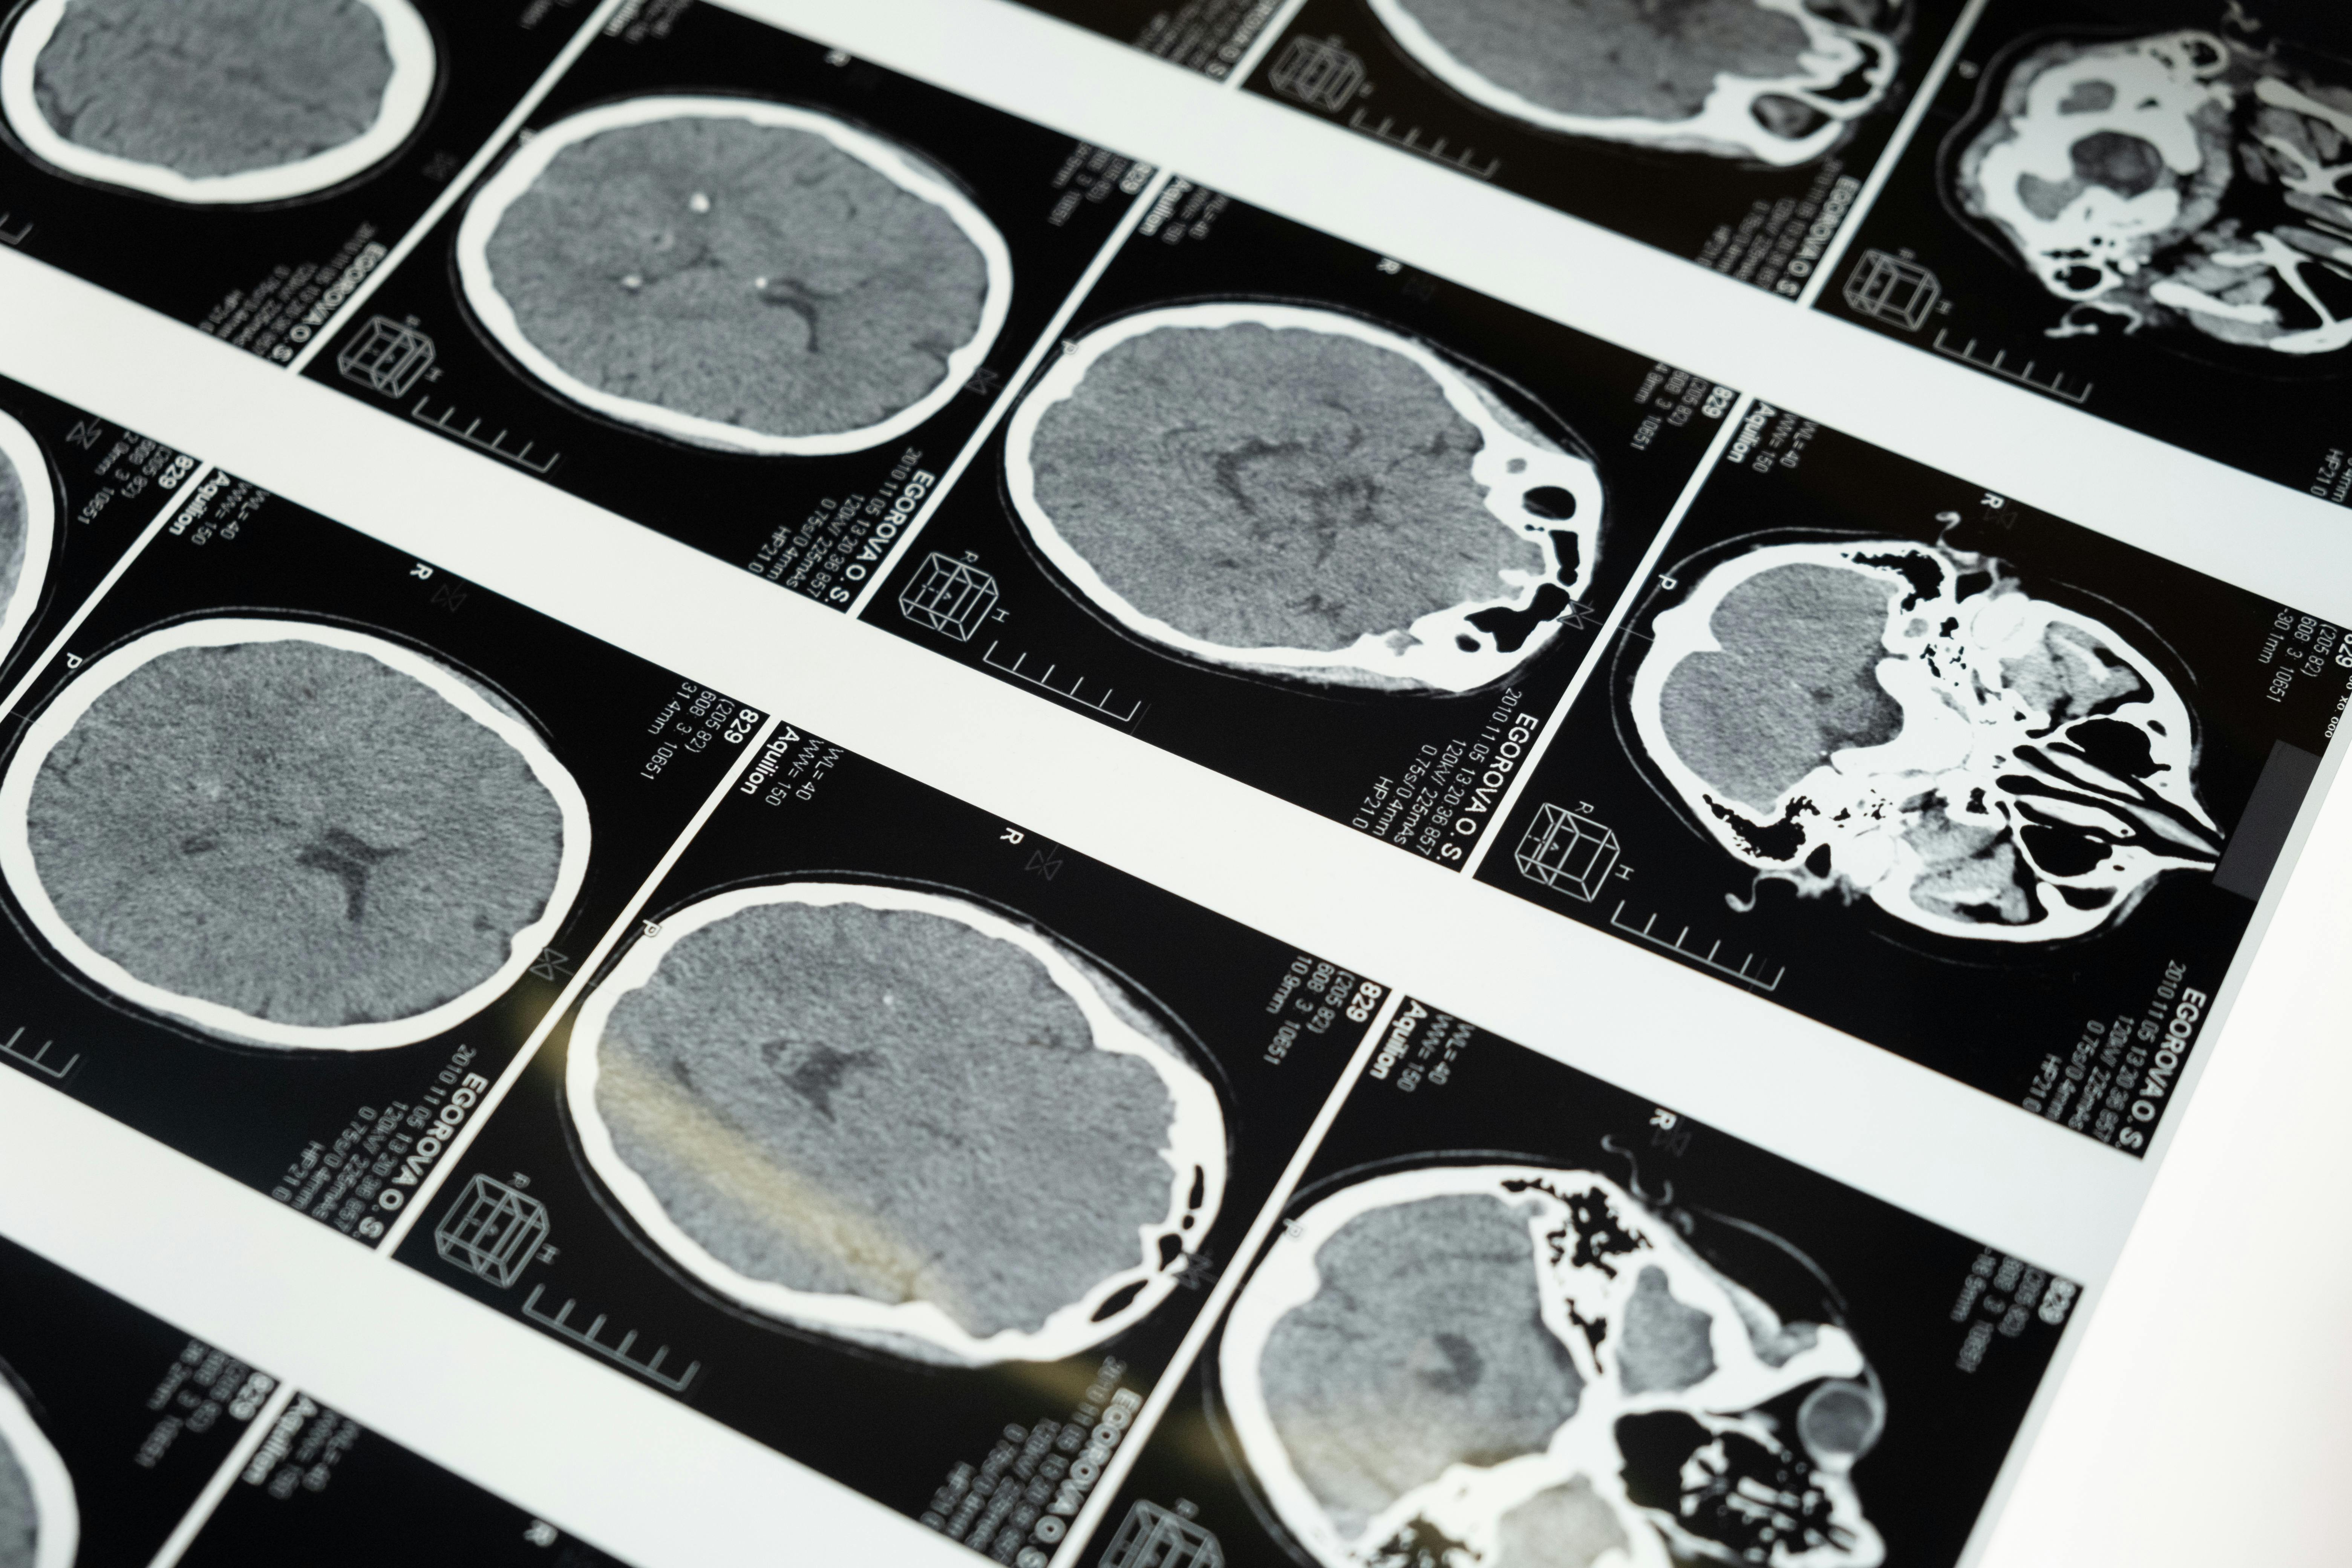

뇌졸중은 크게 허혈성 뇌졸중(뇌경색)과 출혈성 뇌졸중(뇌출혈)로 나뉩니다.